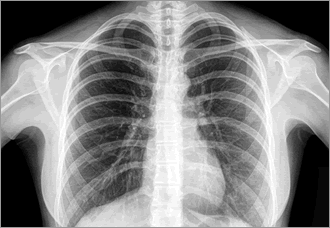

cancer-metastasisがん細胞が転移する臓器を決めている仕組みをマウスの実験で明らかにしたと、コーネル大の星野歩子 (あゆこ) 博士らのがん生物学チームが英科学誌ネイチャーに発表した。